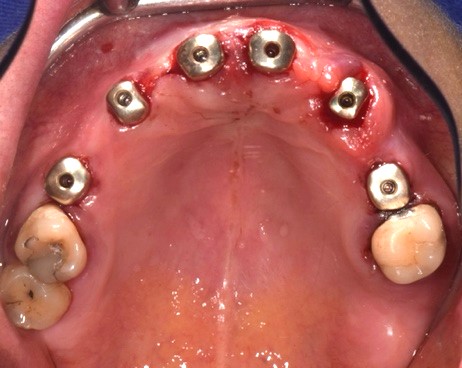

Durante l'intervento chirurgico si posizionava la guida (Fig. 3a) e i siti implantari venivano fresati secondo le sequenze previste. Posizionavamo gli impianti (LYRA ETK, Sallanches, Francia) e gli abutment iPhysio® Profile Designer (Fig. 3 b) che erano selezionati in base al profilo di emergenza desiderato del futuro restauro.

Questi healing abutments vengono avvitati sugli impianti durante la prima o la seconda fase chirurgica. Essi poi restano in posizione durante tutta la guarigione ossea e gengivale e durante la presa dell'impronta, indipendentemente dall'area di impianto. Il Profile Designer iPhysio® viene essere rimosso solo una volta, per posizionare il restauro finale. Gli abutment provvisori in polieter-eter-chetone (PEEK) venivano agganciati agli iPhysio® Profile Designers, sui quali venivano adattati i restauri provvisori (Fig. 3c). Il carico immediato degli impianti è stato eseguito utilizzando una protesi provvisoria in PMMA (Fig. 3d). Al rientro per un controllo, si osservava una corretta guarigione dei tessuti attorno agli impianti e attorno agli abutment iPhysio®.

Fotografia degli impianti appena inseriti con iPhysio® avvitati

Fig. 3(b) Fotografia degli impianti appena inseriti con iPhysio® avvitati.